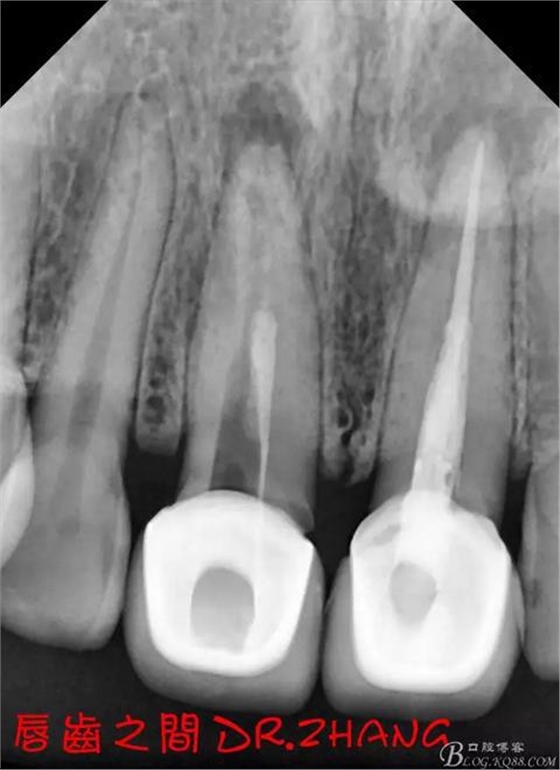

復(fù)診:腫脹明顯消失 患者自訴感覺良好 溝通后決定拆除11 21兩顆烤瓷冠后重新修復(fù) 去冠器直接去冠 去除11根管內(nèi)的充填物 15#K銼疏通根管 11 21根長均為16MM平斷面 薩尼S3系統(tǒng)機擴至2S 期間不斷用氯己定和鹽水交替沖洗 吸潮紙尖干燥根管后06 25#試尖

思博安熱牙膠系統(tǒng)根充 燙斷至根尖三分之一處后纖維樁恢復(fù)牙體組織